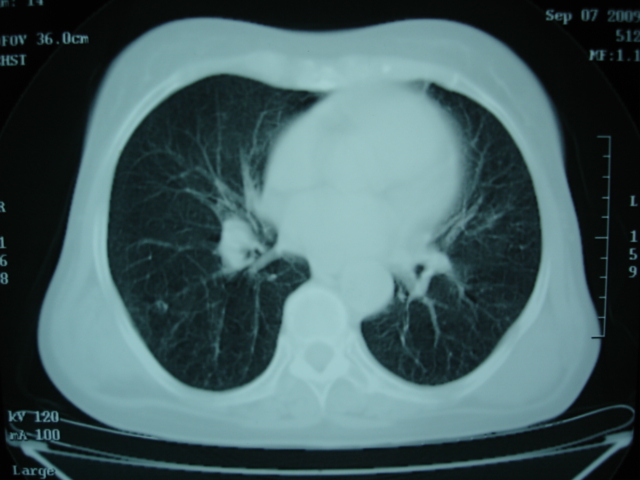

以下是引用卜一在2009-9-7 19:51:00的发言:[br][br] 1 左侧胸内甲状腺占位-多考虑甲状腺腺瘤! 2、左肺门占位-建议增强扫描以便明确性质。 3 慢支并感染! [br]

以下是引用shibing在2009-9-7 20:40:00的发言:[br]左侧胸内甲状腺占位-多考虑甲状腺腺瘤! 2、左肺门占位-建议增强扫描以便明确性质。 3 慢支并感染! [br]